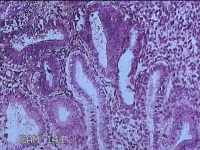

子宫腔赘生物

性别

女

年龄

33岁

临床诊断

子宫内膜息肉?子宫异常出血

一般病史

阴道流血12天。

标本名称

大体所见

灰白粉红色不规则肿物1.5x1.3x0.2cm一堆,表面糜烂。

图2